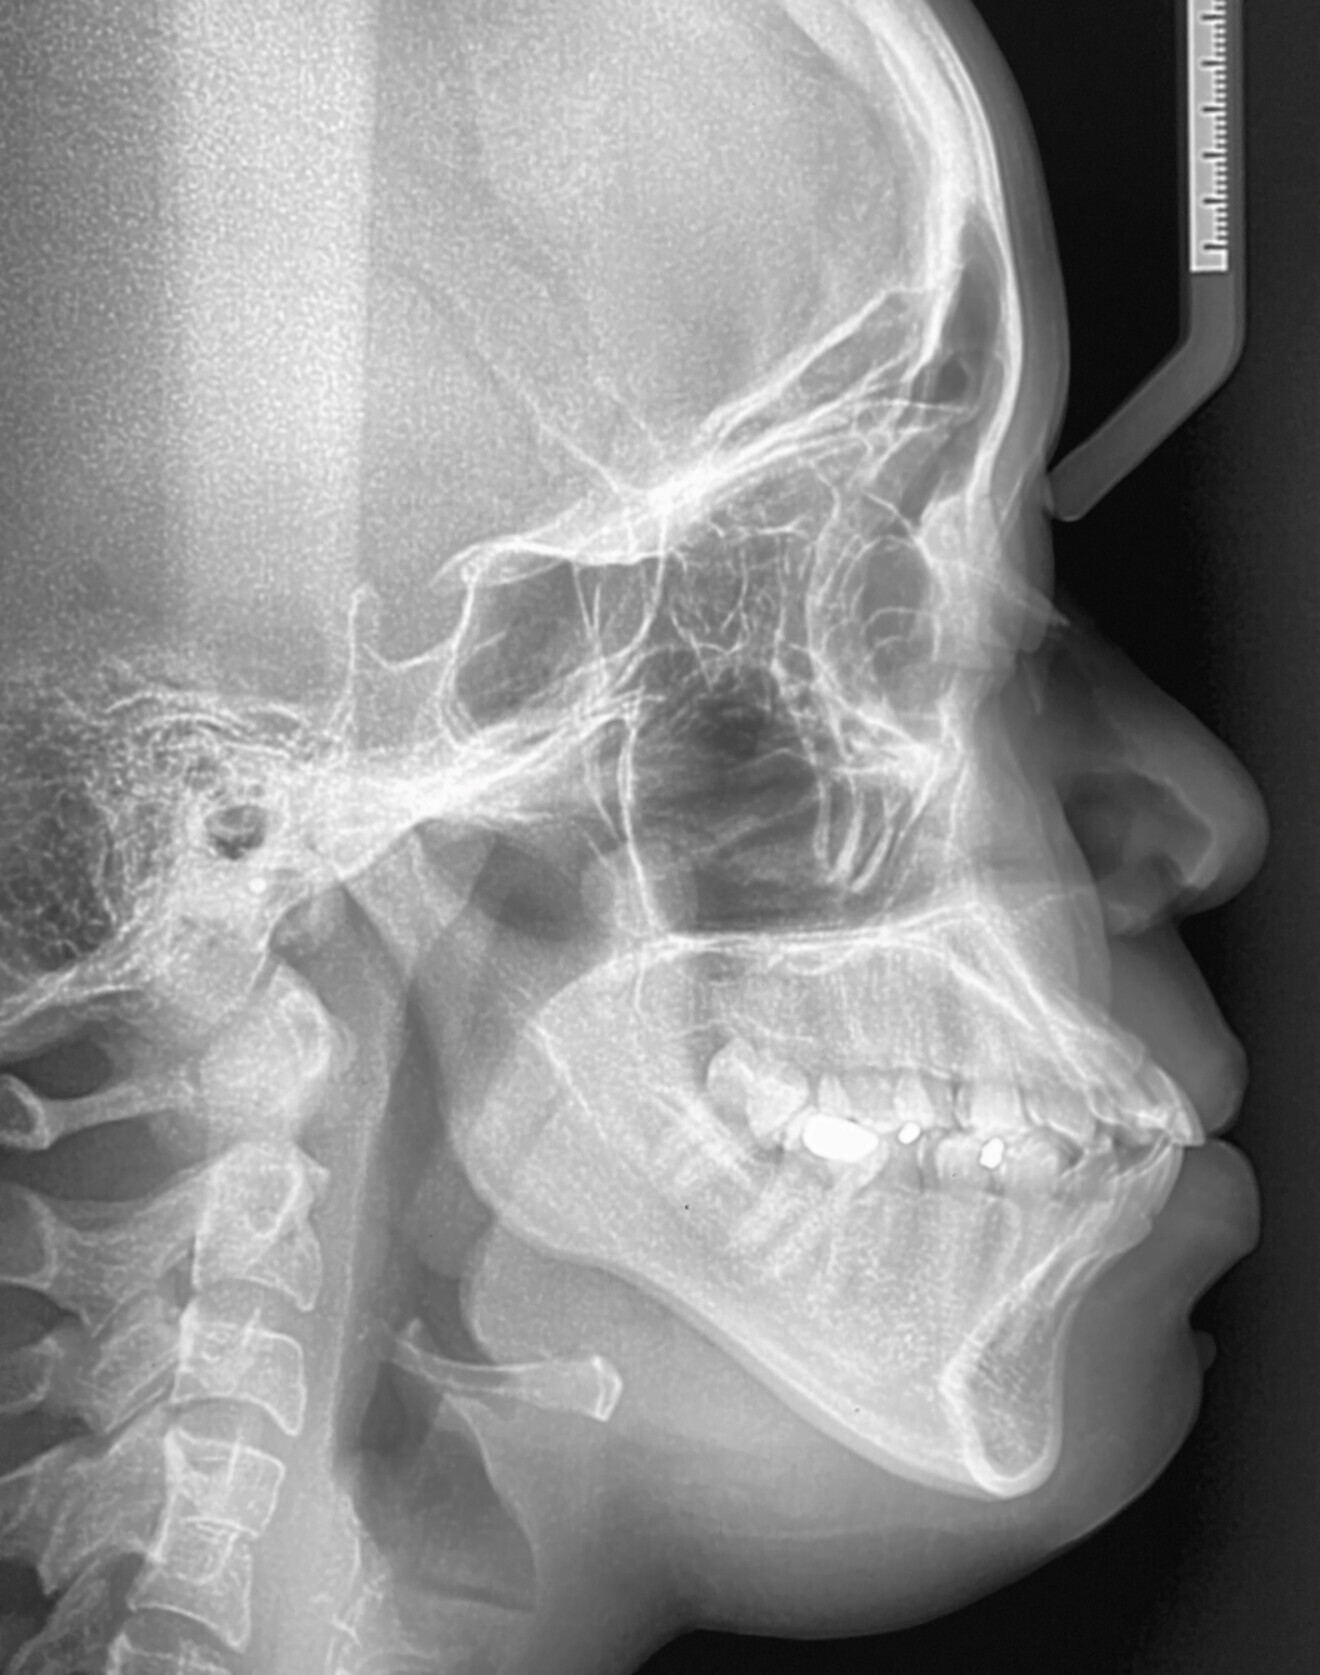

Cephalometric analysis:

Go Me Sn: 42

Saddle: 120

Articular: 144

Gonial: 135

Inner: 399

ANSMe/Nme: 55%

Jarabak Ratio (Sgo/Nme): 58%

Max height: 57

FMA: 30

Normal to high vertical growth pattern

Max height:

SNA: 83

SNB: 79

ANB: 4

Wits: 0mm

McNamara: +2mm

Corpus ratio : 62/72

Max Depth: 94

Holdaway: 7:1

Class II skeletal pattern due to downward rotated mandible.

Long mandibular corpus. Poor pogonion projection

ISN: 112

IMPA: 90

I – I : 113

UI – OP : 50

LI – OP : 65

OP – SN : 18

OP – FH : 15

UI – PP : 122

Increased upper and upright lower incisors.

Normal occlusal plane.